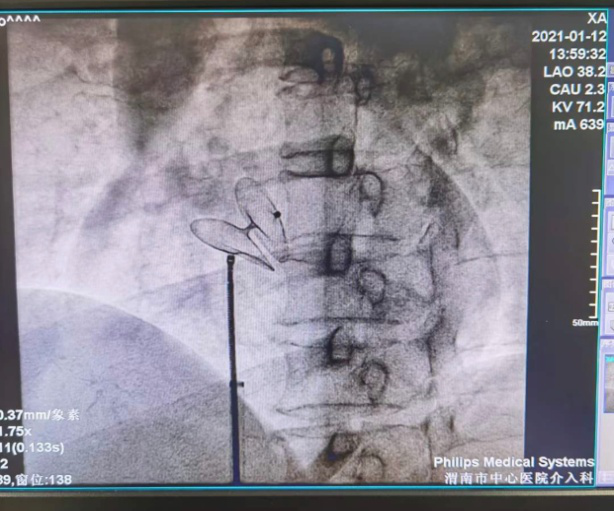

业务范围:常规开展冠状动脉造影术、左心及右心导管检查、食道及心内电生理检查、动态心电图、活动平板运动试验、动态血压监测、核素心肌灌注显像(ECT)检查、多排螺旋CT冠状动脉造影及三维重建术 、超声心动图等检查。熟练开展冠状动脉腔内成形术和支架植入术、冠状动脉内旋磨术、血管内超声(IVUS)指导下复杂冠脉介入治疗、临时及永久性心脏起搏器植入术;先心病房、室缺、卵圆孔未闭的封堵术。全年开展急诊急性心肌梗死介入治疗,每年抢救急性心肌梗死、急性冠脉综合征、急性心力衰竭、严重心律失常等高危患者3000余人。